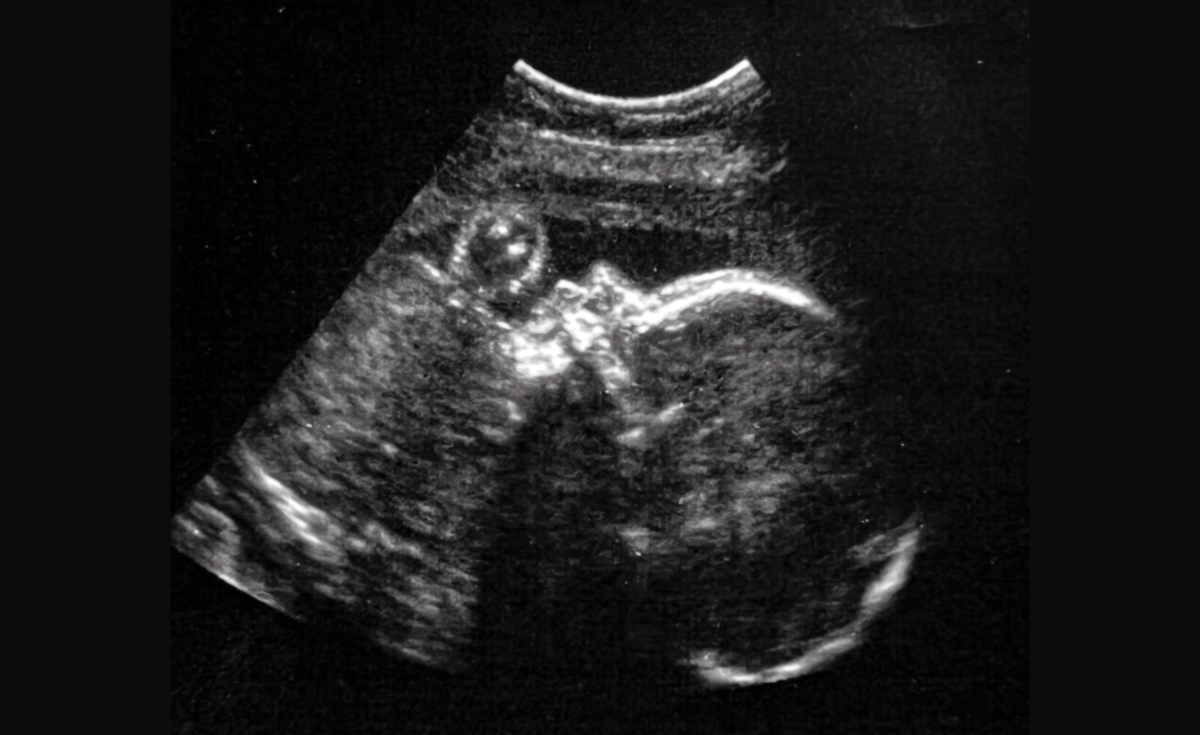

เดนเวอร์ โคลแมนได้รับการวินิจฉัยหลังจากอัลตราซาวน์ว่ามีอาการหลอดเลือดดาเกเลนเมื่ออายุได้เพียง 30 สัปดาห์ ต่อมาในสัปดาห์ที่ 34 ทีมแพทย์ได้ทำการผ่าตัดสมองของเดนเวอร์ โคลแมนผ่านมดลูกของคุณแม่เคนยัตตา โคลแมน